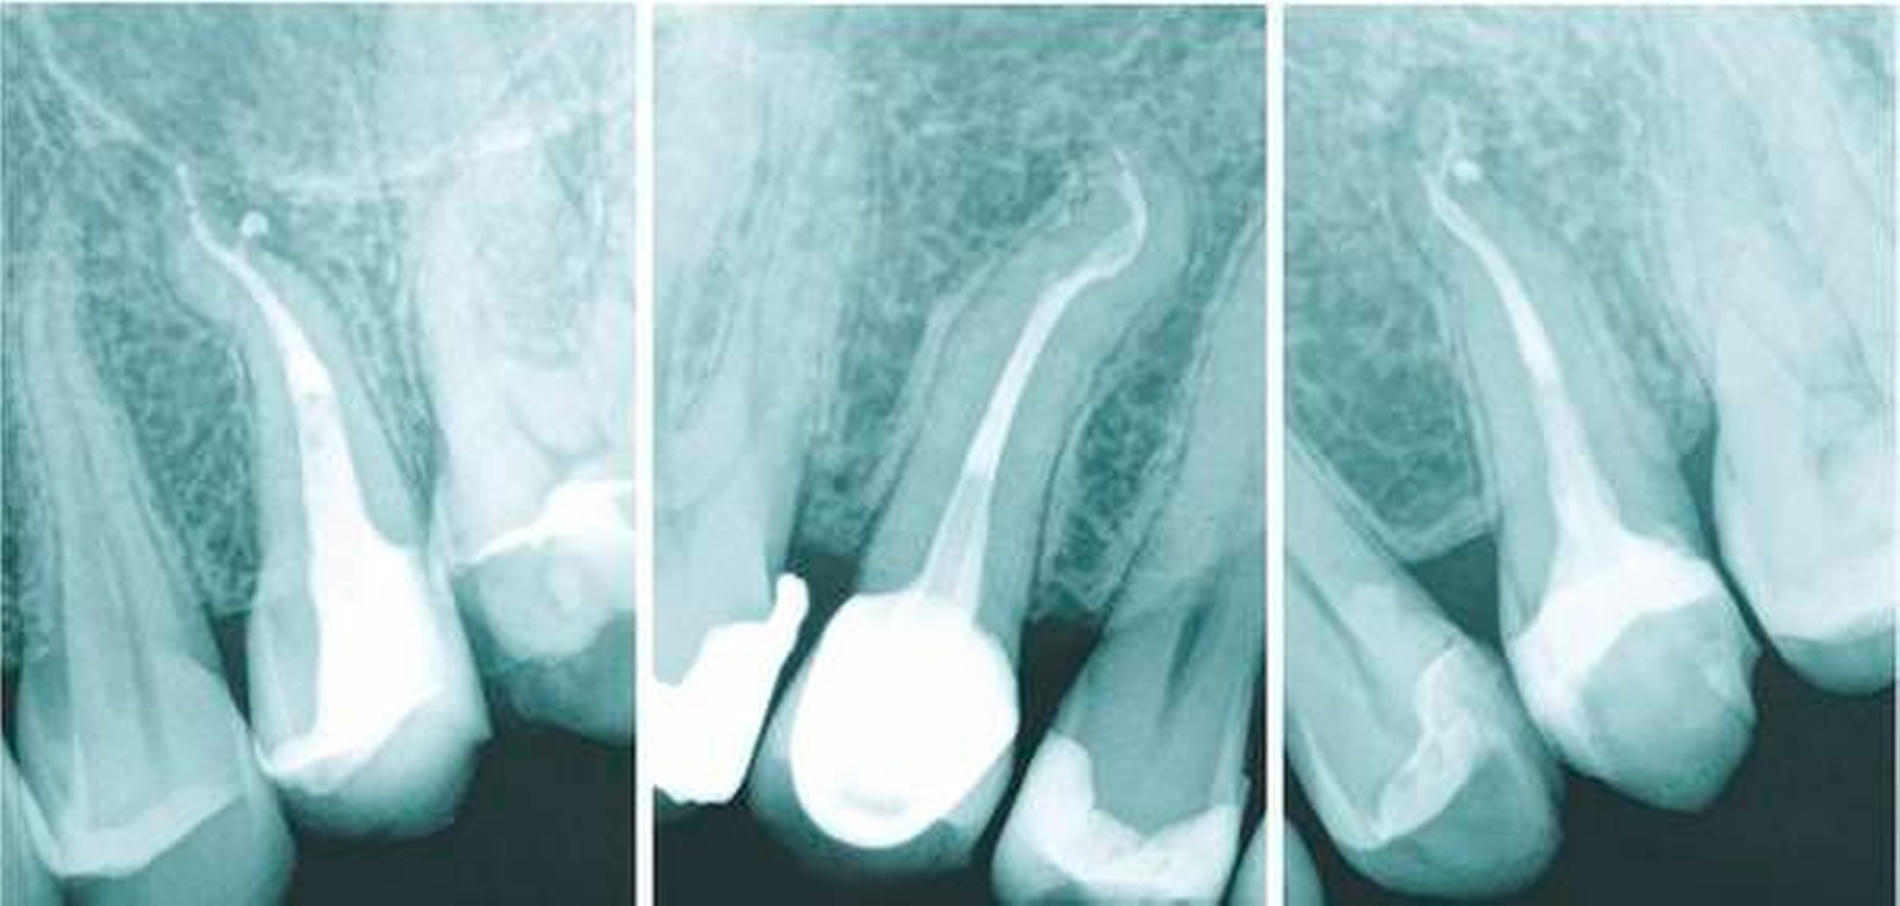

Der obere erste Prämolar hat meistens zwei Wurzeln, der obere zweite Prämolar eine. Hierbei besteht in der Literatur jedoch eine gewisse Uneinigkeit: Zum einen wurden verschiedene Populationen untersucht, zum anderen wurden fusionierte Wurzeln zum Teil unterschiedlich bewertet, das heißt in manchen Studien als ein-, in anderen als zweiwurzlig eingestuft [Bürklein et al., 2017; Tian et al., 2012; Abella et al., 2015] (Abbildung 1). Was die Anzahl der Kanäle angeht, sollte bei beiden Prämolaren grundsätzlich von zwei Kanalsystemen ausgegangen werden. Der Zugang wird daher in beiden Zähnen immer deutlich länglich oval in bukko-palatinaler Richtung präpariert. Ein runder Zugang zum Kanalsystem der oberen Prämolaren führt in vielen Fällen zu einem Übersehen einer der beiden Kanalstrukturen.

Bei einem einwurzligen, zweiten Prämolaren sind die koronalen Kanalsysteme oft schlitzförmig und münden in ein gemeinsames apikales Foramen (Abbildung 5). Gar nicht so selten muss aber mit einer Aufteilung der Kanäle in zwei apikal separat verlaufende Kanalanteile gerechnet werden (Abbildung 6). In der Literatur wird die Häufigkeit des Vorkommens dieser apikalen Aufteilung (Vertucci-Klassifizierungen V, VI und VII) mit bis zu 10 Prozent beziffert [Vertucci, 1984].